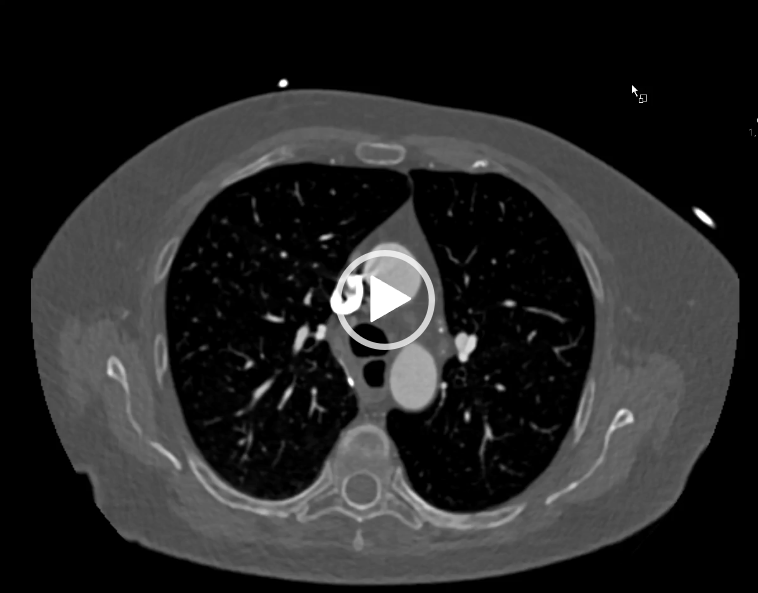

CAZ nr 10: tumoră paracardiacă – şi, incidental, sindrom de ligament arcuat median

Video 1: reconstrucţie axială MIP (maximum intensity projection) din achiziţie angioCT cardiacă cu sincronizare ECG.

Discutie caz nr 10: Se evidentiază o hernie gastrică transhiatală voluminoasă care deplasează anterior cordul şi determină reducerea volumului atriului stâng prin compresie extrinsecă. Incidental, pe imaginile surprinse la nivel abdominal, se evidenţiază sindrom de ligament arcuat median: stenoză de 80-90% a trunchiului celiac proximal prin compresie extrinsecă a ligamentului arcuat median (structură ligamentară ce conectează diafragmul de coloana vertebrală).

Hernia gastrică transhiatală poate fi confundată cu o tumoră paracardiacă.

Sindromul de ligament arcuat median poate fi cauză de dureri abdominale prin ischemie mezenterică.